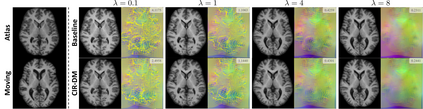

Recent deep learning-based methods have shown promising results and runtime advantages in deformable image registration. However, analyzing the effects of hyperparameters and searching for optimal regularization parameters prove to be too prohibitive in deep learning-based methods. This is because it involves training a substantial number of separate models with distinct hyperparameter values. In this paper, we propose a conditional image registration method and a new self-supervised learning paradigm for deep deformable image registration. By learning the conditional features that are correlated with the regularization hyperparameter, we demonstrate that optimal solutions with arbitrary hyperparameters can be captured by a single deep convolutional neural network. In addition, the smoothness of the resulting deformation field can be manipulated with arbitrary strength of smoothness regularization during inference. Extensive experiments on a large-scale brain MRI dataset show that our proposed method enables the precise control of the smoothness of the deformation field without sacrificing the runtime advantage or registration accuracy.